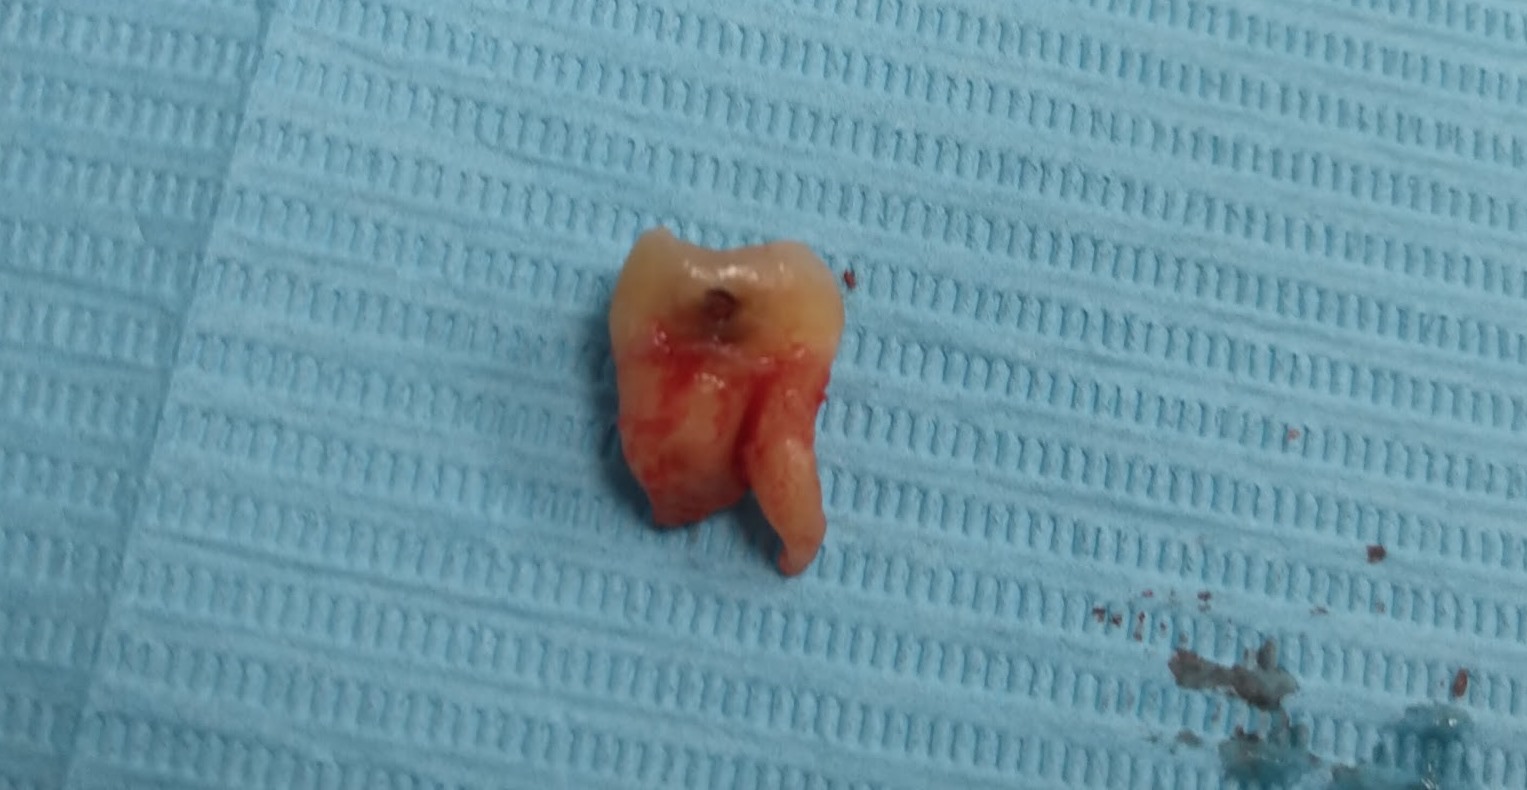

2 зуба мудрости сильно испортились (увидите на фото ниже) - но лечить их никто не хочет (дальше будет понятно почему);

На нижней челюсти удалять зубы мудрости может быть дико больно. У меня был краевой кейс, где якобы было много мелких кривых корней (не все сохранились) и непонятно где проходят нервы. Анестезия заработала, но не с первого и не со второго укола. Ощущения при распиле немного испорченного зуба мудрости без полностью сработавшей анестезии - феерические;

Фотки зубов